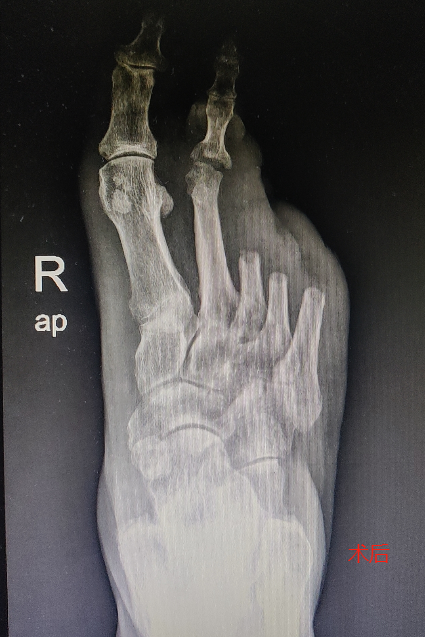

近一年来,她的右足皮肤严重破损、大面积溃烂,不但严重影响了她的行动能力,肢端的疼痛及流脓更是让她倍感痛苦。

经多次对症治疗,效果不佳,最终无奈选择了截肢手术。

尽管已经截肢,但柏女士的糖尿病足伤口愈合仍然困难重重,我院骨科采用了综合治疗方案,其中包括调整降糖方案、改善组织循环和代谢、营养神经、抗炎等治疗手段。经过了一个多月的精心治疗,柏女士的伤口终于愈合了。